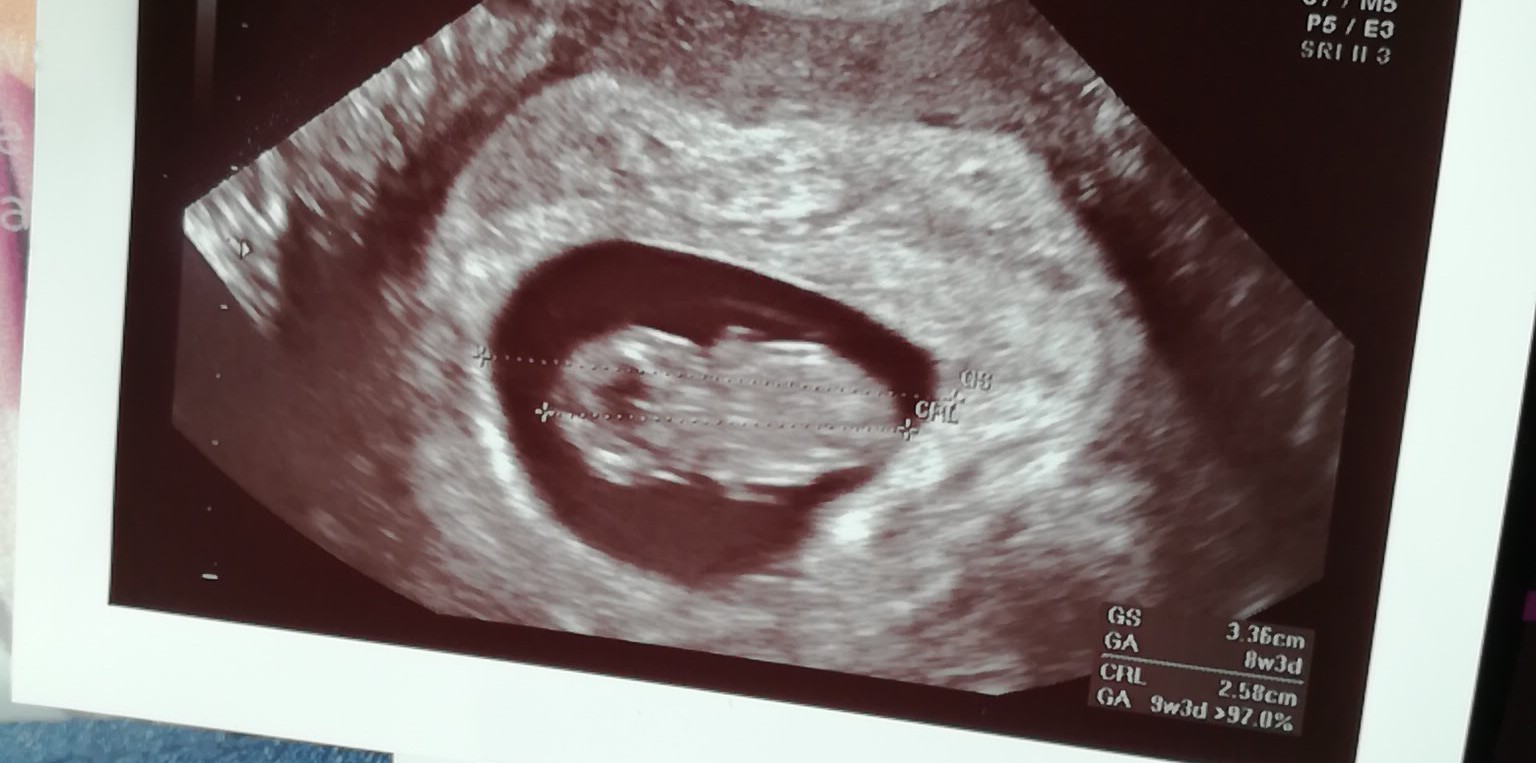

Ja dziś po wizycie drugiej w ciąży, ufff uspokoiłam się i to bardzo słyszałam serce

9 tydzień raczkami ruszał :-) oto dzidziolek mały

Załączniki

• MmsCamera_2020-04-16-11-16-30.jpg

152,2 KB · Wyświetleń: 102